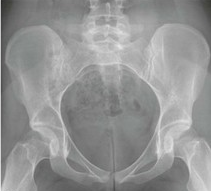

골반뼈를 촬영하여 risser sign 체크하였으며 stage 5 로 잔여성장 가능기간 거의 없음의 소견이었습니다. 앞으로 1~2cm정도의 잔여성장만 할 뿐이며 최종 예상키 163~164cm로 예측되었습니다.